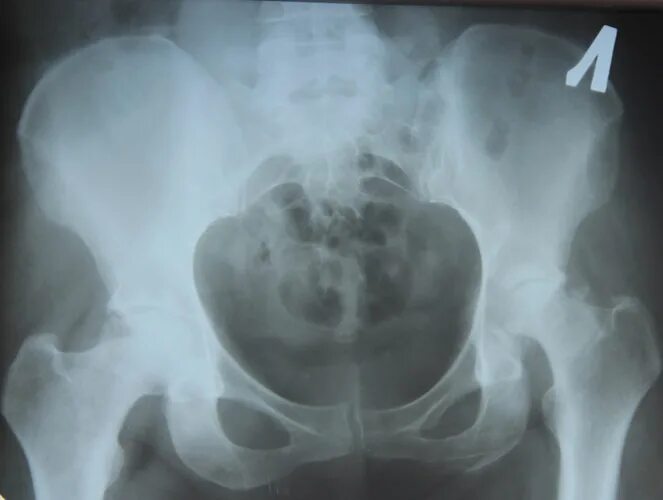

Метастазы в тазобедренном